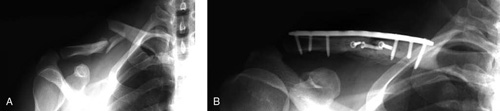

(A) The clavicle is broken in more than one place and the fragments are severely out of alignment. (B)The fractured pieces are held in place by a combination of plates and screws.

Reproduced with permission from Bahk MS, Kuhn JE, Galatz LM, Connor PM, Williams GR: Acromioclavicular and sternoclavicular injuries and clavicular, glenoid, and scapular fractures. Instructional Course Lectures, Vol. 59. Rosemont, IL, American Academy of Orthopaedic Surgeons, 2010, p 215.